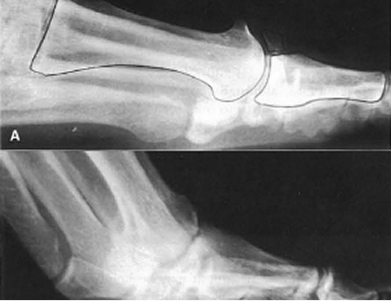

Osteotomy Surgery for Bunions

An osteotomy can be performed for other conditions, not just bunions. The term osteotomy refers to any surgery where bones are reshaped, but when talking about bunions, an osteotomy is performed to remove a bit of bone to help realign the toe and support the joint. Typically, pins and screws will be used to support the newly aligned bone and to keep the toe straight.

An exostectomy is the surgery to remove the bony bump that defines the bunion. This surgery is often just one part of the bunion surgery and is paired with soft tissue procedures and a technique to straighten the toe and support joint health. Removing the bunion lump alone will not solve the problem. As you can see from x-rays, bunions include significant shifts in how the toe bone lies. To fully solve a bunion, other steps must be taken to straighten the toe.